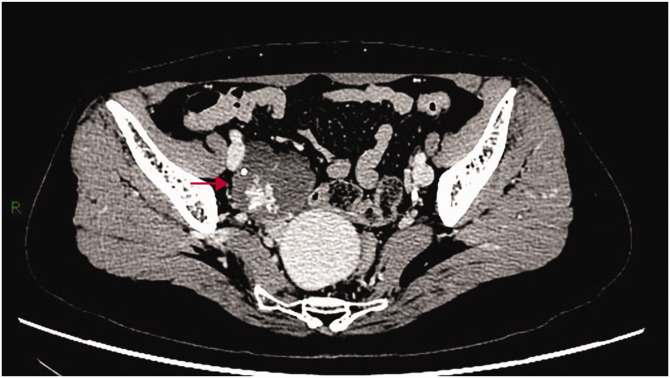

Ovarian hemangioma is an extremely rare benign tumor in clinical practice. We report the case of a postmenopausal woman presenting with vaginal bleeding, in whom imaging revealed a right adnexal mass. Surgical excision of the adnexa was performed, and pathological examination confirmed a right ovarian hemangioma. Concurrent findings included endometrial polyps and cervical polyps.